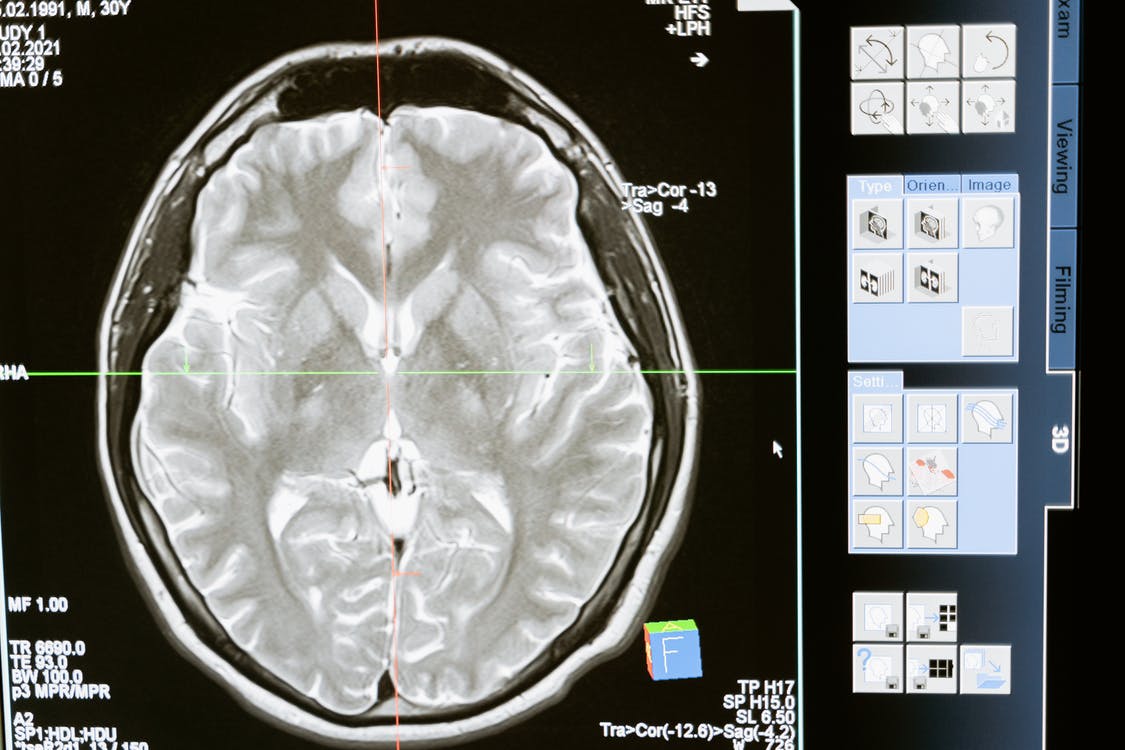

Neurological injuries can have serious long-term negative effects on a person’s health. Classifying head trauma as a neurological injury can mean brain trauma, spinal cord damage, skull fractures, broken bones in the spine, and destruction of the peripheral nerves. There are several ways that a person can suffer a neurological injury such as after a car accident, from a sporting event, or from exposure to toxins.

How Do You Know if You Have a Neurological Injury?

Acquired brain injury takes place when the brain is denied oxygen and is damaged as a result. The symptoms of an acquired brain injury are similar to those that take place after a TBI.